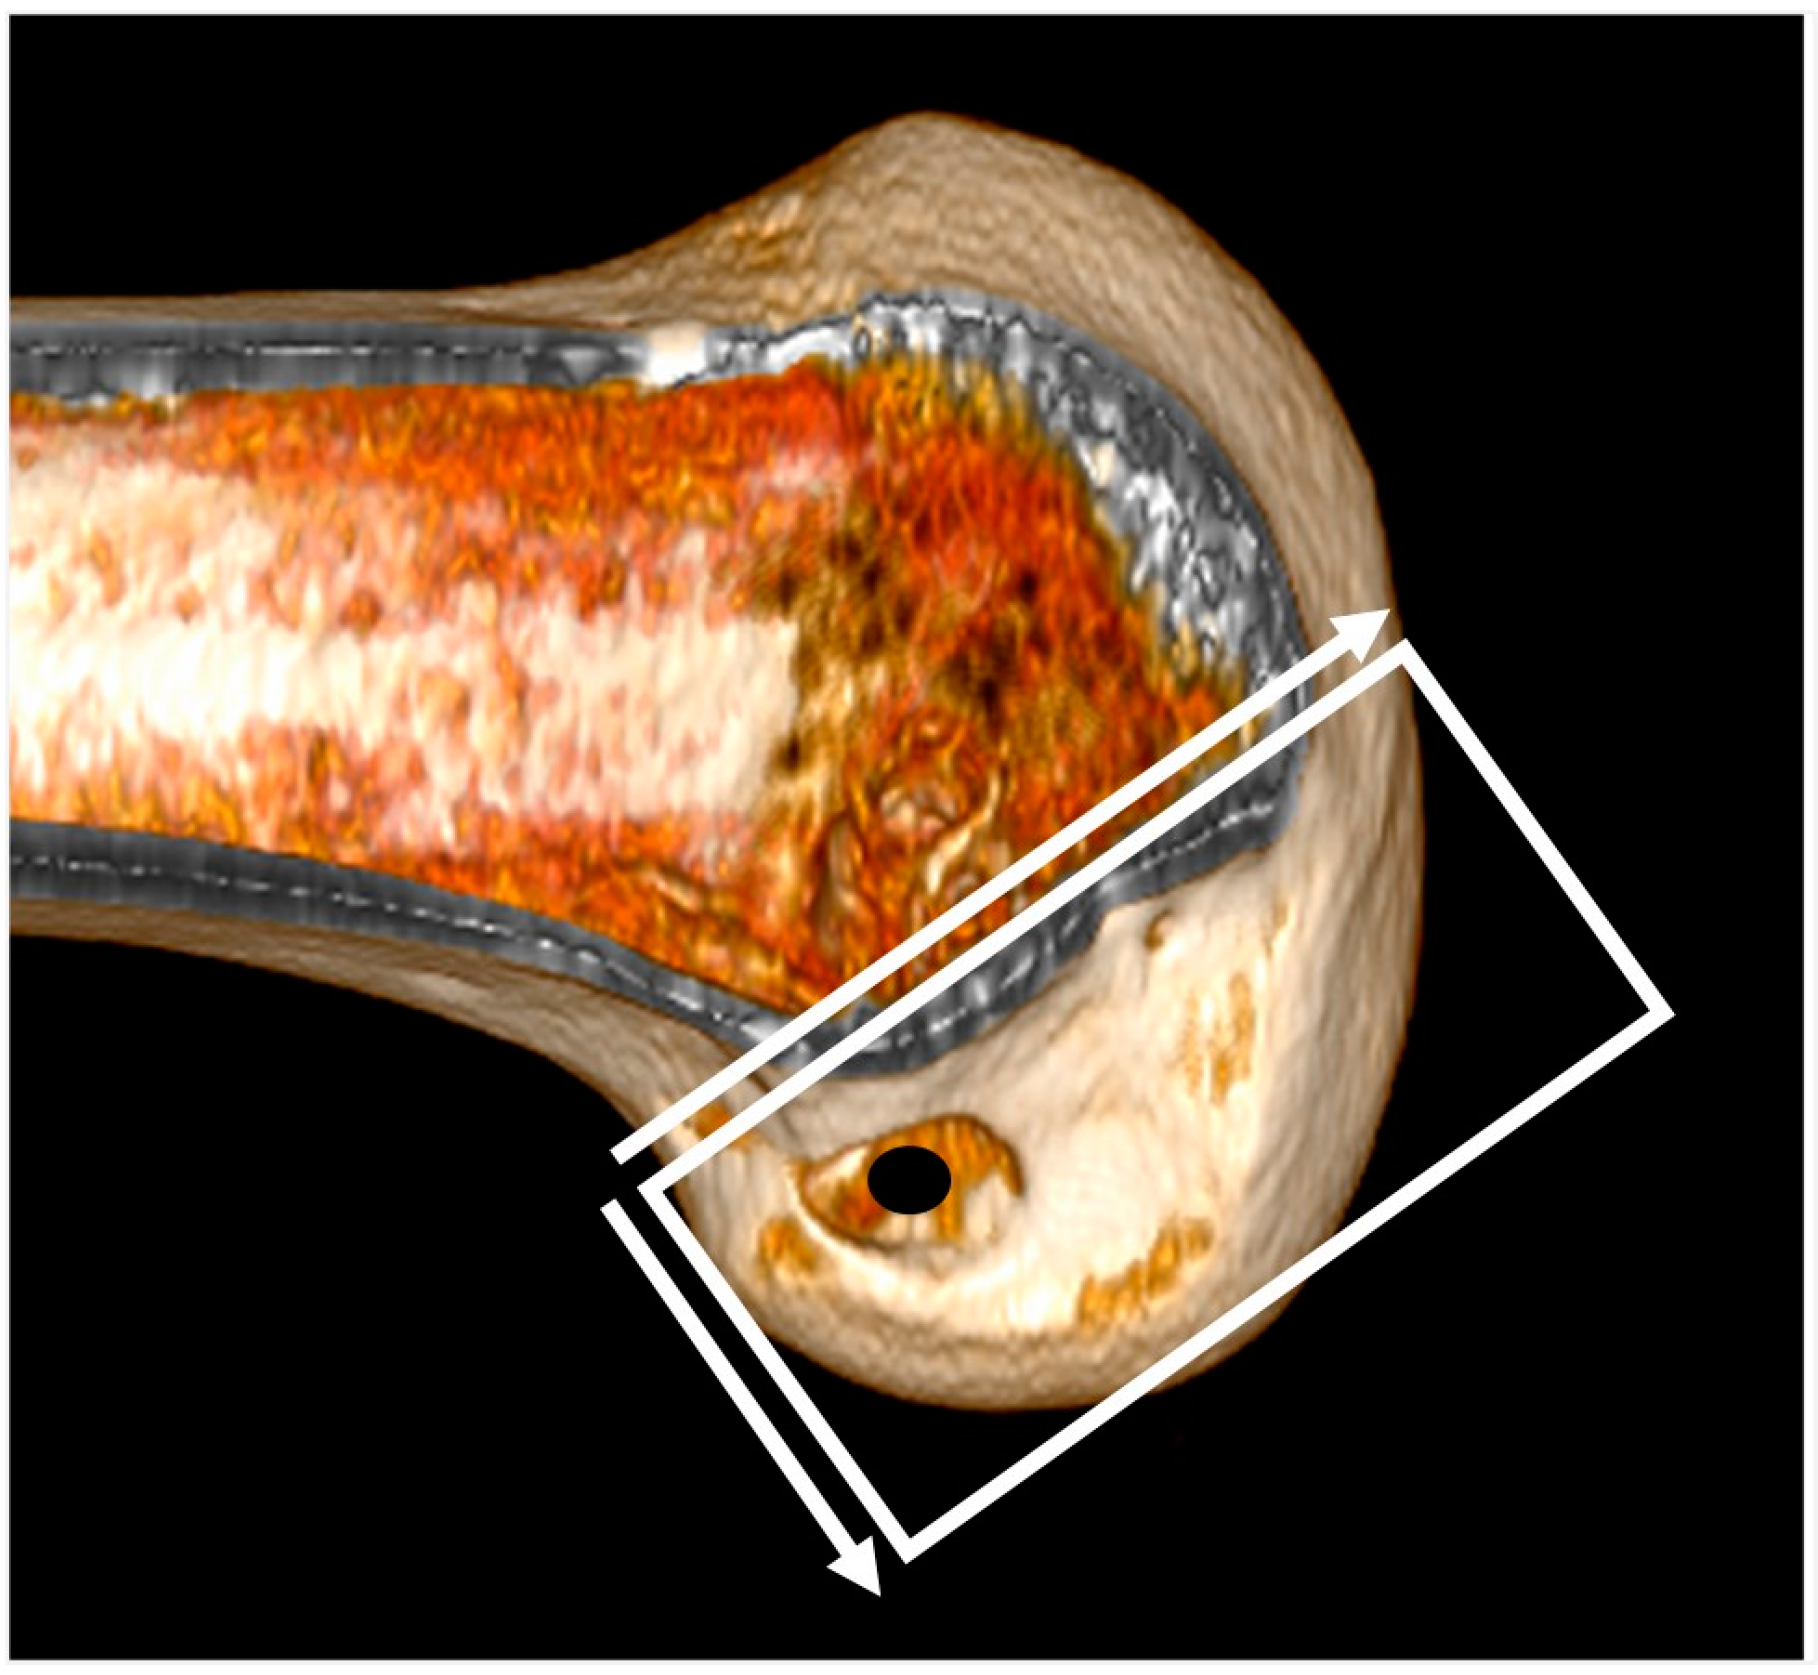

The 3D CT scans were imported into 3D software (AW Sever 3.2 PACS system, GE Healthcare; Chicago, IL, USA) for the assessments of the femoral graft bending angle and femoral tunnel length. The femoral graft bending angle was defined as the angle formed by the longitudinal axis of the femoral tunnel and the line connecting the intra-articular aperture of the tibial tunnel and the intra-articular aperture of the femoral tunnel (Figure 3). The femoral tunnel length was defined as the distance between the center of the extra-articular aperture of the femoral tunnel and the center of the intra-articular aperture of the femoral tunnel in a plane where the entire femoral tunnel could be viewed (Figure 4). Posterior wall breakage of the femoral tunnel was also checked.

Figure 3.

The femoral graft bending angle is defined as the angle formed by the longitudinal axis of the femoral tunnel and the line connecting the intra-articular aperture of the tibial tunnel and the intra-articular aperture of the femoral tunnel.